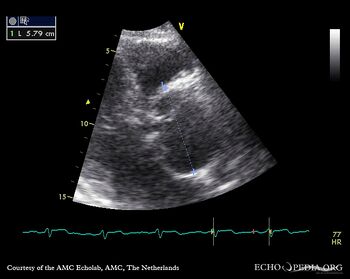

| Courtesy of: AMC Echolab, AMC, The Netherlands | |

| PLAX: dilated aortic root, dissection flap in ascending aorta | PLAX: diameter of aortic root |